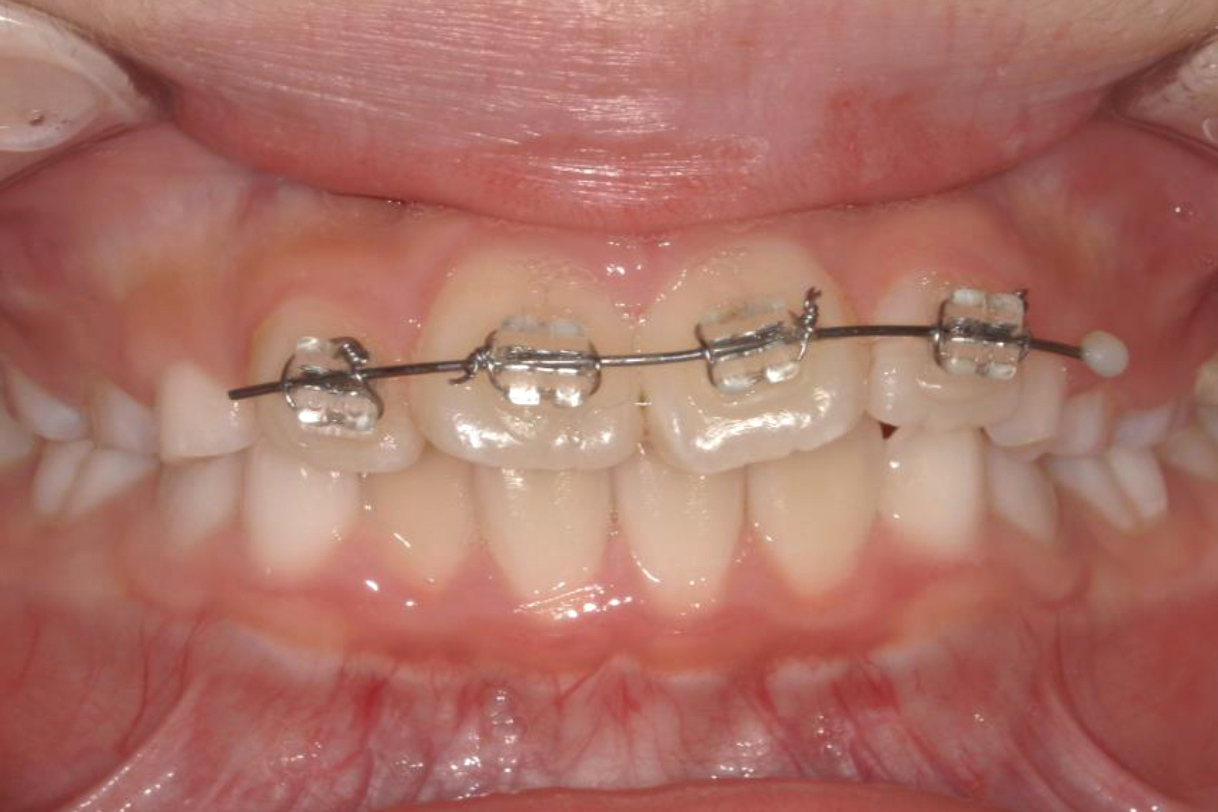

初診時年齢:7歳

治療:前歯部矯正

治療法:上顎前歯部表側の装置

治療期間:2ヶ月

費用:110,000円(税込)

リスク・副作用:装置装着による違和感、歯の移動時の痛み